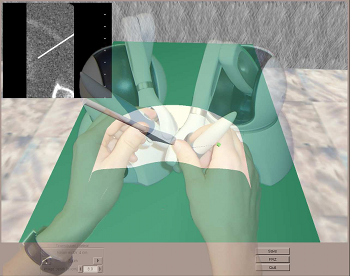

P. F. Villard, F. P. Vidal, L. ap Cenydd, R. Holbrey, S. Pisharody,

Purpose: Training in Interventional Radiology currently uses the apprenticeship model, where clinical and technical skills of invasive procedures are learnt during practice in patients. This apprenticeship training method is increasingly limited by regulatory restrictions on working hours, concerns over patient risk through trainees’ inexperience and the variable exposure to case mix and emergencies during training. To address this, we have developed a computer-based simulation of visceral needle puncture procedures. Methods: A real-time framework has been built that includes: segmentation, physically based modelling, haptics rendering, pseudo-ultrasound generation and the concept of a physical mannequin. It is the result of a close collaboration between different universities, involving computer scientists, clinicians, clinical engineers and occupational psychologists. Results: The technical implementation of the framework is a robust and real-time simulation environment combining a physical platform and an immersive computerized virtual environment. The face, content and construct validation have been previously assessed, showing the reliability and effectiveness of this framework, as well as its potential for teaching visceral needle puncture. Conclusion: A simulator for ultrasound-guided liver biopsy has been developed. It includes functionalities and metrics extracted from cognitive task analysis. This framework can be useful during training, particularly given the known difficulties in gaining significant practice of core skills in patients. Keywords: Biomedical computing, Image segmentation, Simulation, Virtual reality |

P.-F. Villard, F. P. Vidal, C. Hunt, F. Bello, N. W. John, S. Johnson, and

Purpose: We present here a simulator for interventional radiology focusing on percutaneous transhepatic cholangiography (PTC). This procedure consists of inserting a needle into the biliary tree using fluoroscopy for guidance. Methods: The requirements of the simulator have been driven by a task analysis. The three main components have been identified: the respiration, the real-time X-ray display (fluoroscopy) and the haptic rendering (sense of touch). The framework for modelling the respiratory motion is based on kinematics laws and on the Chainmail algorithm. The fluoroscopic simulation is performed on the graphic card and makes use of the Beer-Lambert law to compute the X-ray attenuation. Finally, the haptic rendering is integrated to the virtual environment and takes into account the soft-tissue reaction force feedback and maintenance of the initial direction of the needle during the insertion. Results: Five training scenarios have been created using patient-specific data. Each of these provides the user with variable breathing behaviour, fluoroscopic display tuneable to any device parameters and needle force feedback. Conclusions A detailed task analysis has been used to design and build the PTC simulator described in this paper. The simulator includes real-time respiratory motion with two independent parameters (rib kinematics and diaphragm action), on-line fluoroscopy implemented on the Graphics Processing Unit and haptic feedback to feel the soft-tissue behaviour of the organs during the needle insertion. Keywords: Interventional radiology; Virtual environments; Respiration simulation; X-ray simulation; Needle puncture; Haptics; Task analysis |

We present an integrated system for training visceral needle puncture procedures. Our aim is to provide a cost effective and validated training tool that uses actual patient data to enable interventional radiology trainees to learn how to carry out image-guided needle puncture. The input data required is a computed tomography scan of the patient that is used to create the patient specific models. Force measurements have been made on real tissue and the resulting data is incorporated into the simulator. Respiration and soft tissue deformations are also carried out to further improve the fidelity of the simulator. Keywords: Physically based modelling, Virtual reality |

We present an integrated system for training ultrasound guided needle puncture. Our aim is to provide a cost effective and validated training tool that uses actual patient data to enable interventional radiology trainees to learn how to carry out image-guided needle puncture. The input data required is a computed tomography scan of the patient that is used to create the patient specific models. Force measurements have been made on real tissue and the resulting data is incorporated into the simulator. Respiration and soft tissue deformations are also carried out to further improve the fidelity of the simulator. Keywords: image guided needle puncture training, interventional radiology training, needle puncture |